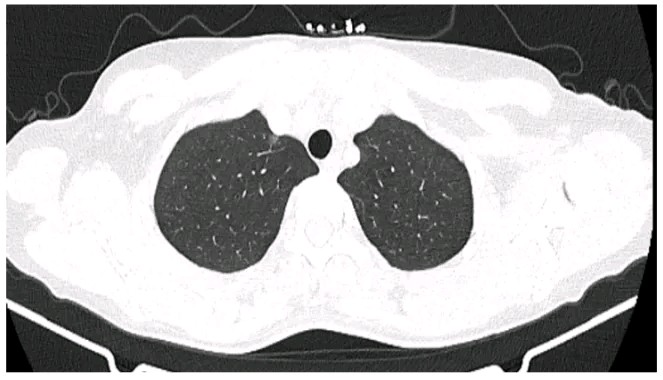

因为担心,王女士今年的例行体检果断选择了胸部 CT,结果发现右肺上叶尖后段胸膜下磨玻璃结节影(0.6 cm × 0.5 cm)(见图 1),她无吸烟史,没有肿瘤家族史,下一步她该怎么办呢?手术还是随访观察?

图 1